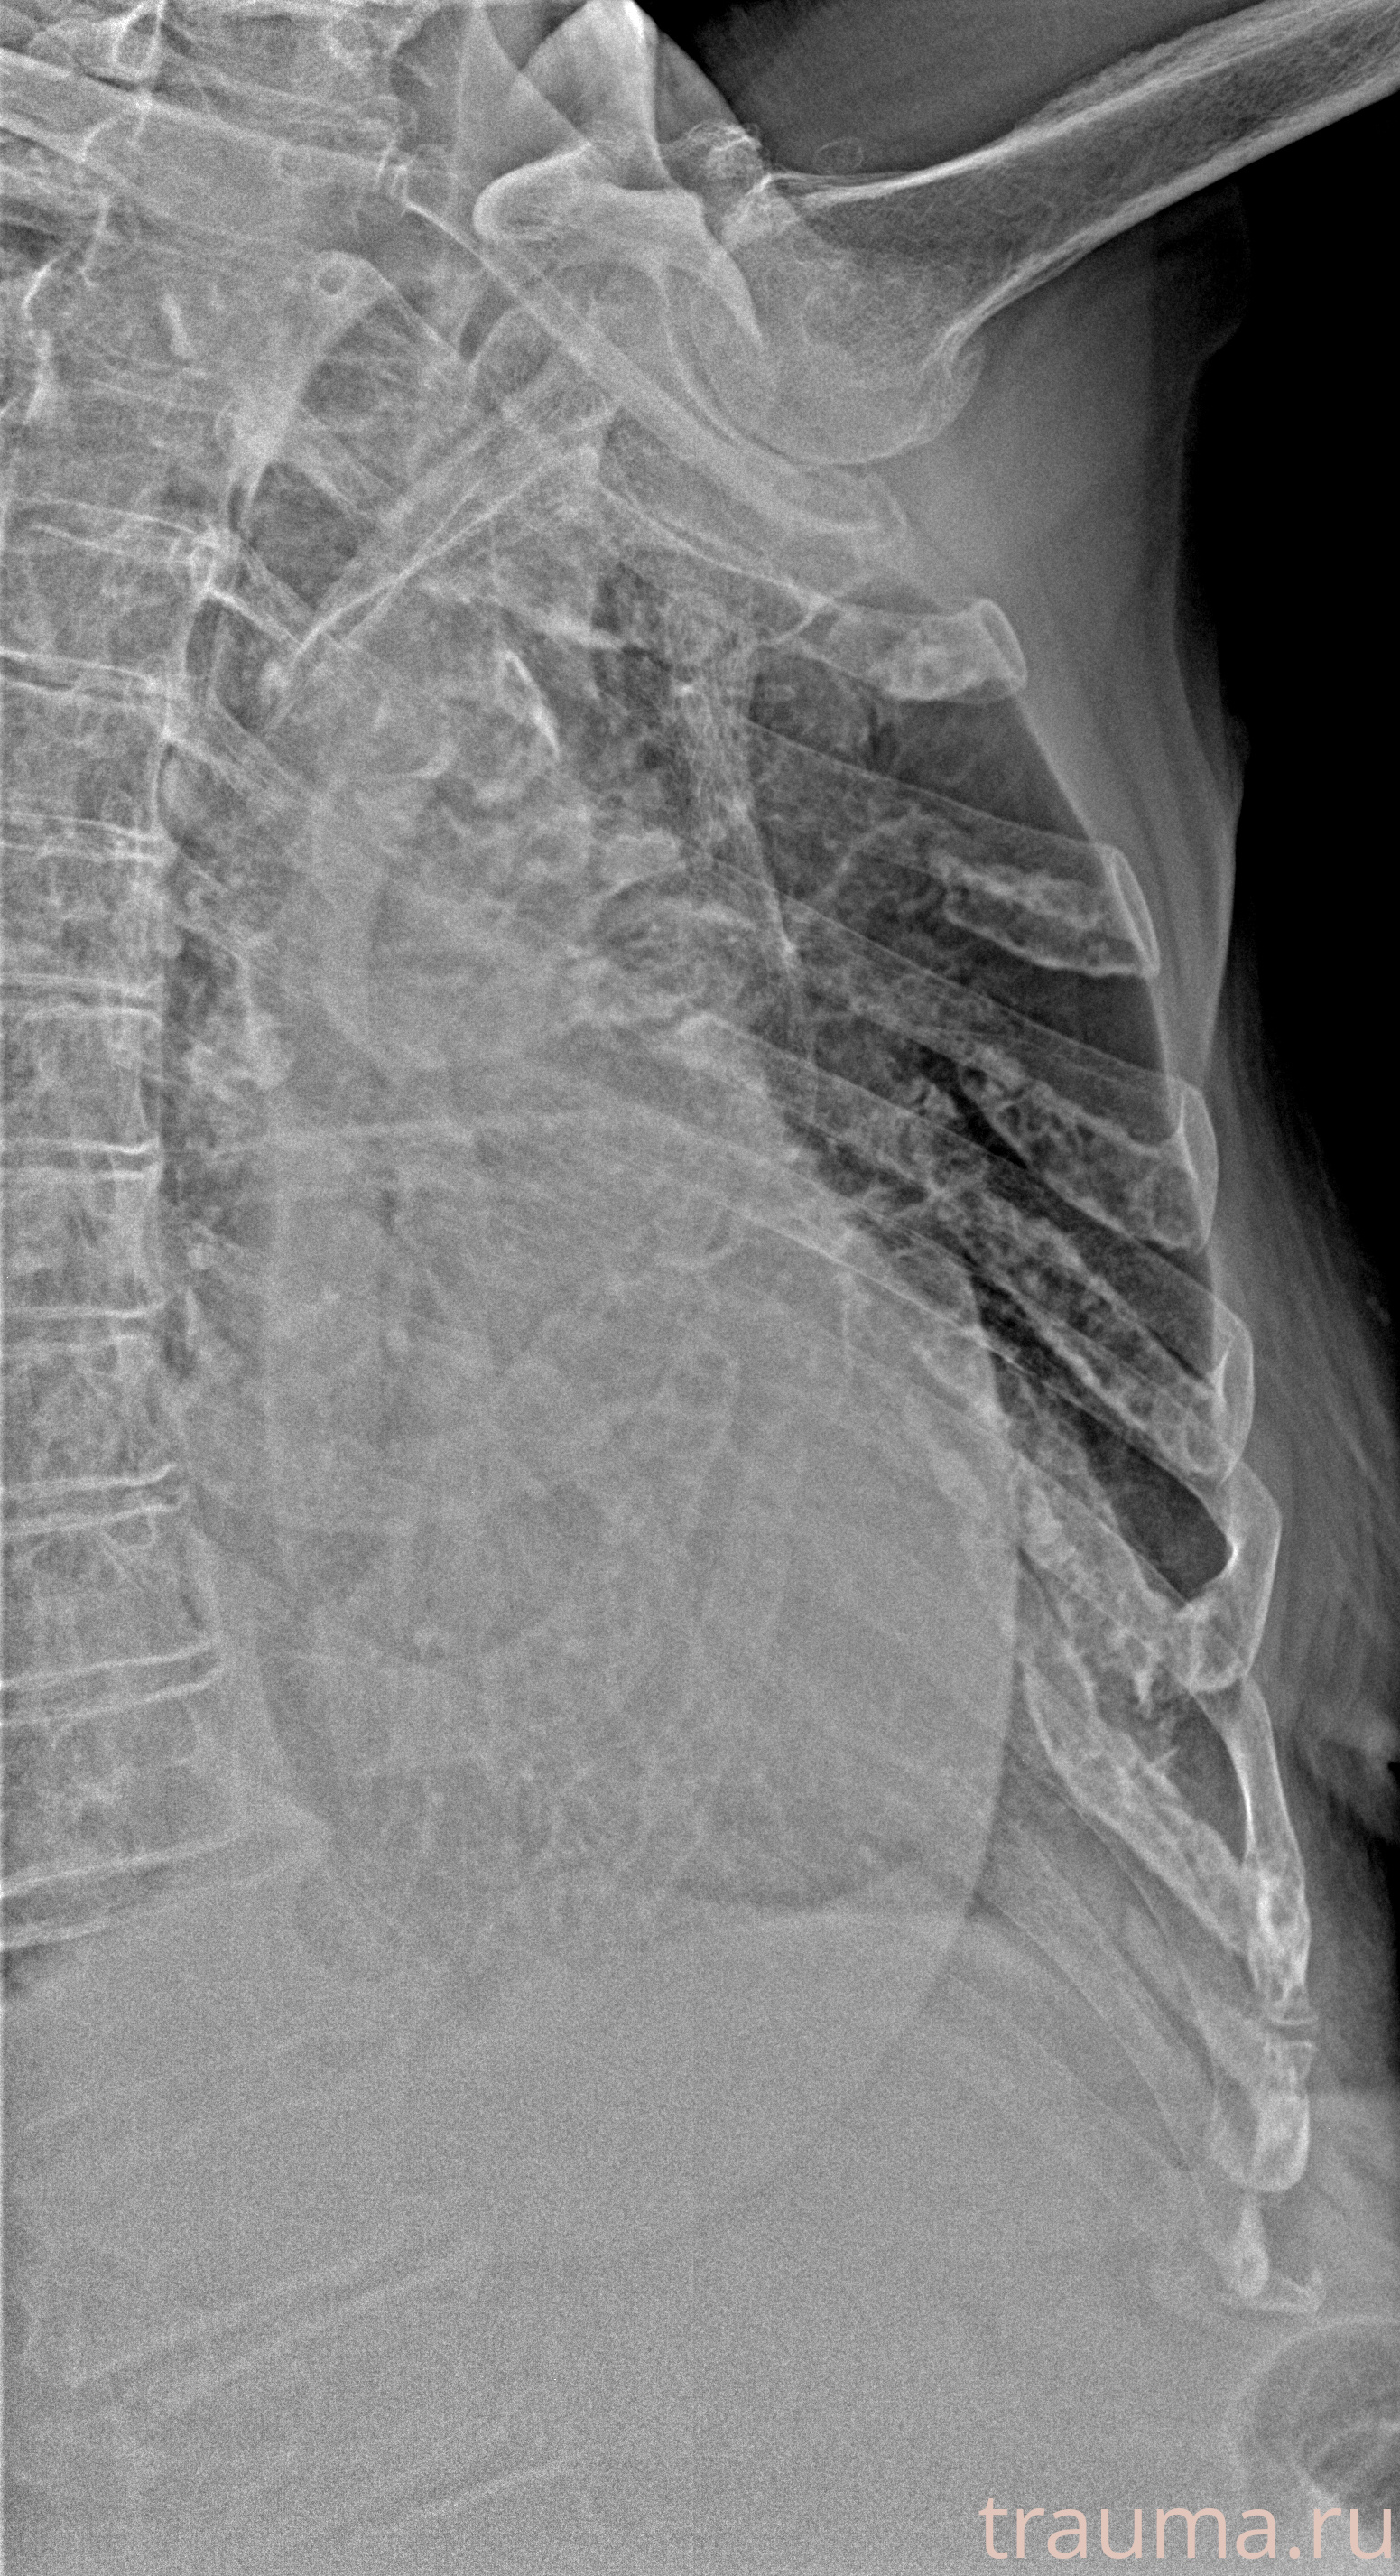

Рентген на дому: по вашему адресу приезжает врач-рентгенолог, травматолог-ортопед с мобильным рентгеновским аппаратом, проводит диагностику травмы или заболевания, делает необходимые рентгенограммы, дает рекомендации по дальнейшему лечению. Получить качественные снимки в домашних условиях возможно благодаря уникальной методике, разработанной МосРентген Центром для института  Склифосовского